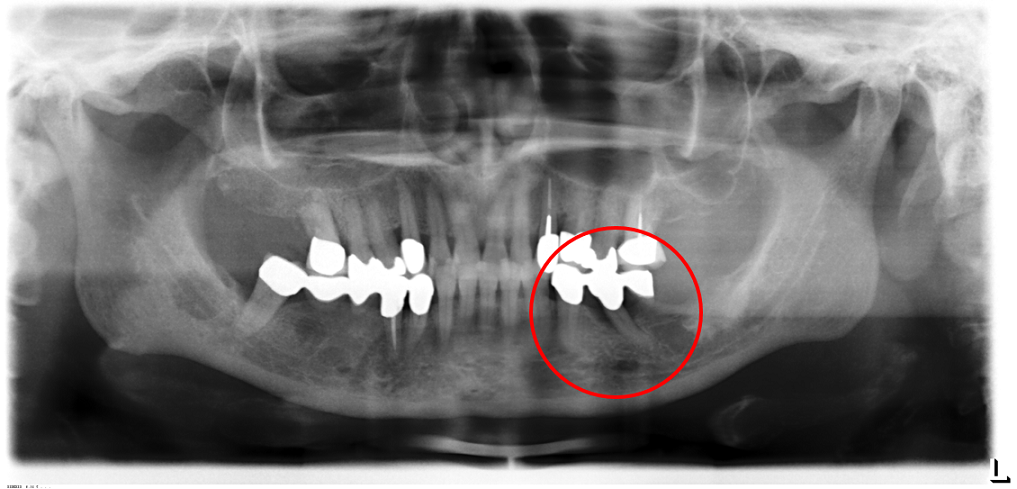

01/02 - Radiographic view before periodontal regenerative therapy with Straumann® Emdogain®. A deep intrabony defect appeared mesially and distally on the left mandibular first premolar. Pre-surgical probing measured 8 mm. The defect morphology presented as well-contained.

Contained intrabony defect treated using Straumann® Emdogain® - Prof. Dr. Dr. A. Kasaj